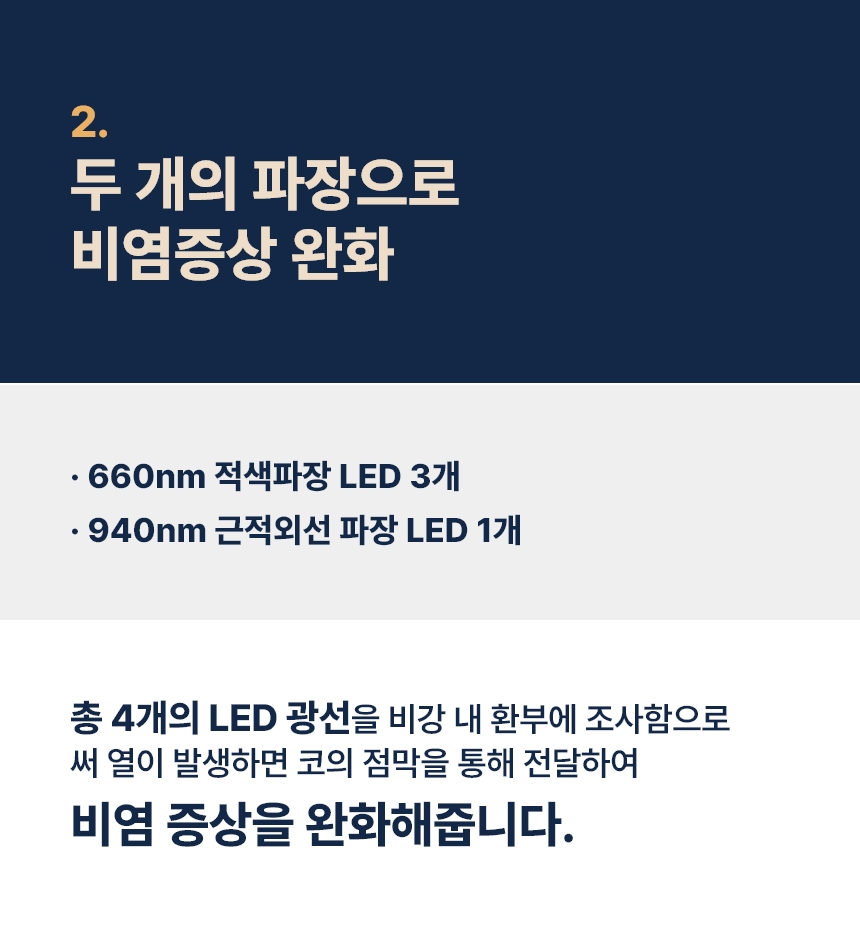

현재 특허 등록된 광 에미터 기술은 광 에미터(광가이드)를 이용해 LED를 외부에 두어 저항에 의한 발열을 콧속에 넣지않고, 비염에 도움이 되는 적색과 적외선 광선만 조사하는 방법입니다.

“LED는 빛도 나오지만 열도 나옵니다. 기기 끝에서 LED 빛이 나오면서 비강 점막을 건조시킨다는 부작용이 있었어요. 이를 개선하기 위해 무발열 광 에미터 기술을 적용했습니다. 광케이블처럼 LED 빛이 전파되는 통로를 만들어주는 방식이에요. 이비인후과에서 쓰는 광 치료기가 1세대, 기존 가정용 광치료기가 2세대라면 무 발열 광에미터 기술은 3세대라고 할 수 있죠.”